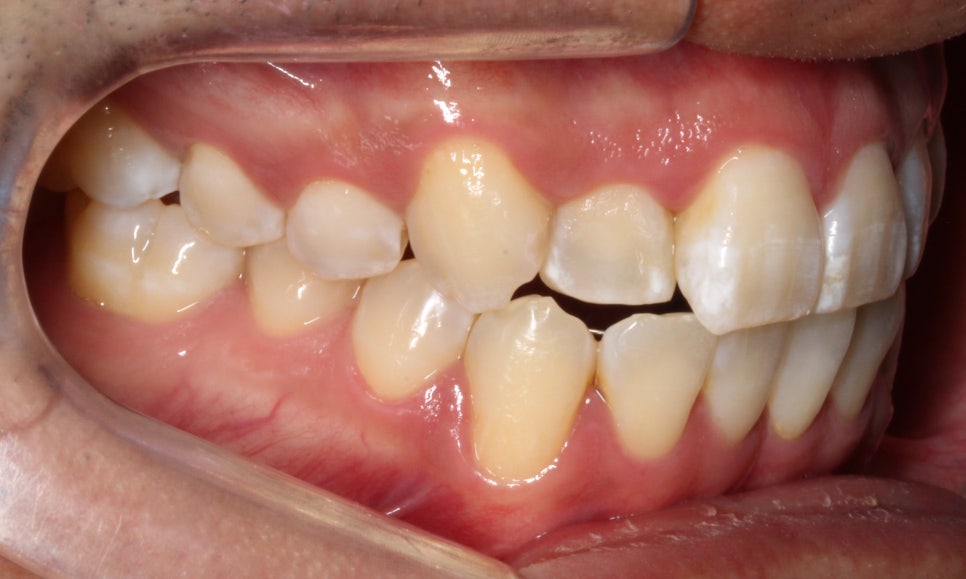

이번에는 덧니 고민으로 오신 환자분인데요.

윗니 오른쪽 두 번째 앞니가 들어가 있고,

다른 앞니끼리도 너무

세게 닿아서 고민이라고 오셨어요.

사진을 보실 땐

눈에 보이는 방향의 왼쪽이

환자에게는 오른쪽입니다.

#12 치아는 안으로 들어가 있었습니다.

환자분은 #13 이 튀어나왔다고 생각하시던데,

이렇게 씹는 면 사진으로 보면

#13이 튀어나왔다라기보단

#12가 상대적으로 들어가 있는 게 맞죠.